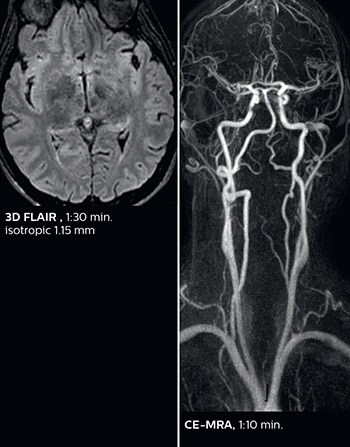

According to Dr. Savatovsky, Ingenia Elition has an impact in virtually all examinations. “We can either make the scanning faster compared to our older Ingenia 3.0T, or we save enough time so that we can add sequences we wouldn’t perform otherwise, or increase resolution. So, I think it has benefits for most of our patients.” “Some routine exams that we use every day have been shortened since we started using Elition. For example, we now use mostly a comprehensive stroke protocol (high b-value diffusion, fast 3D FLAIR, TOF, supra-aortic vessels angiography, SWIp, T1 post gad) that lasts 10 to 11 minutes, but our fast stroke protocol takes only 7 minutes. Our routine IAC needs about 10 minutes scan time and our comprehensive brain MS examination requires no longer than 13 minutes of scan time. Our ability to reduce acquisition times of most sequences helps to shorten total examination times, which in turn helps us to increase the number of patients we scan per day. “The main breakthrough for us was that Compressed SENSE and Multiband SENSE have allowed us to accelerate our examinations. Alternatively, we can invest the time gained in obtaining higher spatial resolution to see more details, or we can add additional sequences,” says Dr. Savatovsky. “That’s a big improvement from what we did before.”

The MRI center at Fondation Rothschild receives several neuro and head/neck emergency cases per day. On weekdays, an average of 7 unscheduled patients will require scanning, with approximately 4 to 5 patients actually requiring an urgent MRI scan, according to Dr. Savatovsky. He notes that the ability to accelerate sequences while maintaining image quality is particularly important in the emergency setting. “The fast scanning capabilities that came with Elition allow us to do a really quick examination and answer a lot of questions within a short time. We use every tool available to accelerate image acquisition while maintaining a reasonable image quality. So, for most of the sequences we use Compressed SENSE, for example, in our 3D FLAIR, in contrast-enhanced and noncontrast MR angiography, and for susceptibility-weighted sequences.” Among the emergencies that are routed to the MRI department at Fondation Rothschild, stroke is seen almost daily. “After arriving, acute stroke patients are immediately brought to the MRI preparation room and positioned on the FlexTrak table. There, the neurologist examines the patient and the biological workup is performed. Once this is finished, we can immediately move the patient with FlexTrak into the MRI and begin the scanning within one or two minutes. So, having the FlexTrak is a big advantage for us.”

Dr. Savatovsky appreciates the improvements and flexibility that Elition with Compressed SENSE and MultiBand SENSE provides, particularly for stroke patients. “For stroke, it allows us to cut about 5 minutes off of our stroke protocol, or to keep the same acquisition time and get more insights.” The ability to perform more sequences can help in making a swift and confident diagnosis. “For example, our stroke cases usually include the regular sequences that every center does (b1000 diffusion, FLAIR, time-of-flight angiography), but we also image supra aortic vessels, and we can replace a gradient echo sequence with a fast 50-second susceptibility-weighted sequence, and all of this doesn’t add much time. because all the regular sequences are accelerated on Elition.” “The time savings with Compressed SENSE and MultiBand SENSE make it easier to add sequences to give us additional insights. Depending on the context and the first results, we might add a DSC perfusion to assess the ischemic penumbra, an ASL perfusion to help find an alternative cause in case of normal diffusion, or add a high-resolution T1 sequence for a stroke patient, to quickly assess wall imaging in emergency cases. The additional sequences can help improve patient management, because we can already consider some alternative diagnoses if the morphological MRI is normal.”